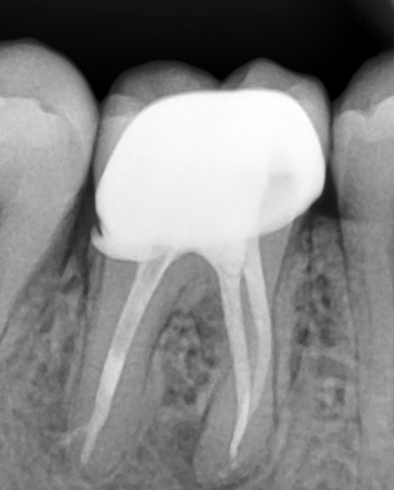

Mulți dintre dinții tratați sau retratați, sunt infectați sau prezintă o leziune inflamatorie periapicală (Fig. 4.9.6), de aceea evoluția cazului spre succes depinde foarte mult de îndepărtarea microorganismelor din sistemul canalar. Irigarea copioasă ne ajută, mai ales în cazul canalelor curbe și pentru a evidenția, curăța și obtura și anumite canale secundare ce sunt blocate de resturi dentinare (Fig. 4.9.7). Astfel, se reduce flora microbiană din sistemul canalar și din țesuturile adiacente favorizând vindecarea osoasă, situație observată după 6 luni în acest caz. (Fig. 4.9.8)